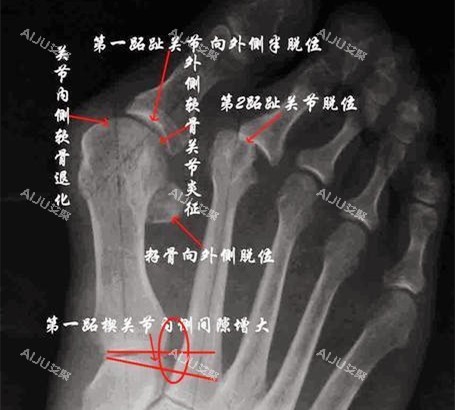

大脚骨,医学上称为拇外翻,是一种常见的足部畸形问题。

它不仅影响脚部的美观,还会导致疼痛、行走不便等问题,严峻影响患者的生活质量。